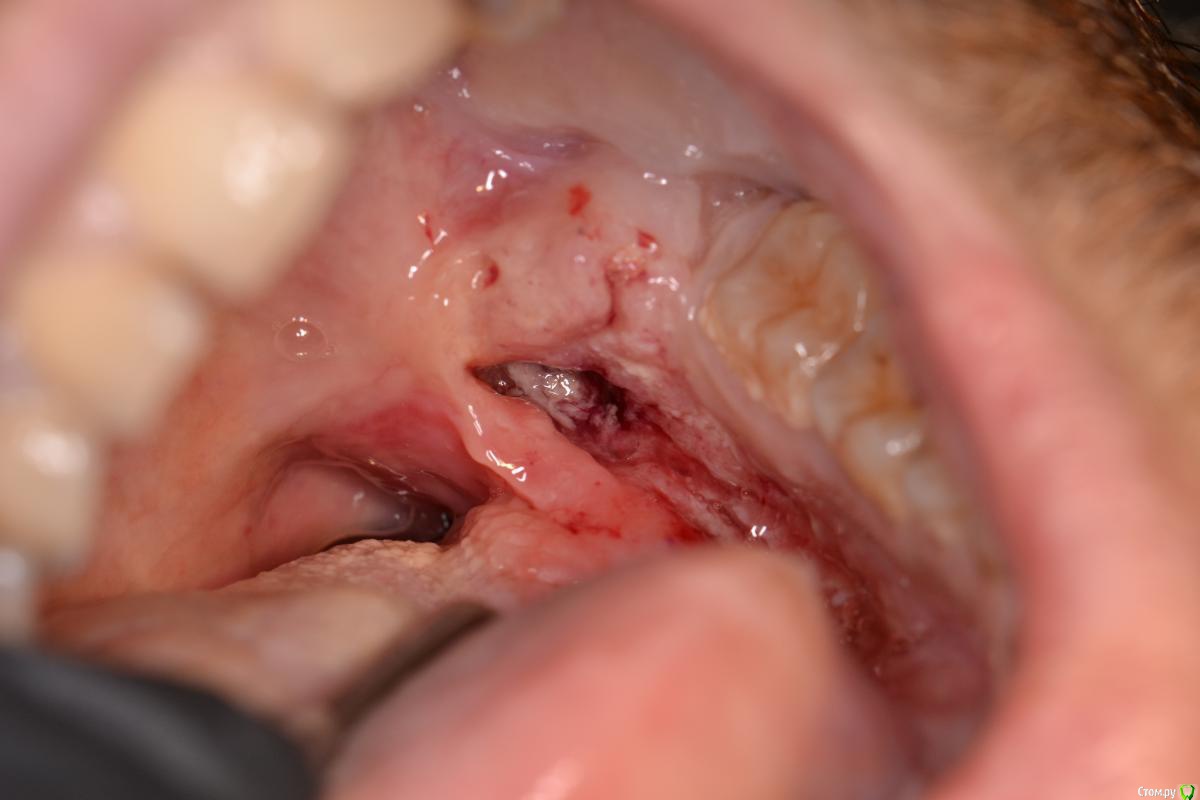

TIGER Опубликовано 22 декабря, 2016 Поделиться Опубликовано 22 декабря, 2016 Пациент 30 лет...жалобы на боли,затрудненное открываение рта...объективно на фото,при осмотре был удалён секвестр...заподозрил плохое...отправил в стационар...сегодня ответ....Cr...будьте бдительны при диагностике.... Ссылка на комментарий

Тимур86 Опубликовано 27 декабря, 2016 Поделиться Опубликовано 27 декабря, 2016 Вставлю свои 5 копеек.Остеосаркома.Изменения на слизистой пациент начал отмечать после травматичного удаления 46-го примерно год назад.http://s018.radikal.ru/i526/1612/83/be427148e9e5.jpg http://s018.radikal.ru/i522/1612/09/7624b427a4fb.jpg http://s019.radikal.ru/i602/1612/86/f393c6dc1767.jpg http://s019.radikal.ru/i643/1612/3f/aa9028208553.jpg http://s008.radikal.ru/i305/1612/84/ad71b30f876d.jpg Ссылка на комментарий